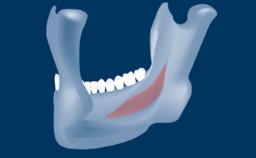

In this short microlearning module on digitally guided sinus floor elevation, we delve into a specialized aspect of the digital workflow for implant-guided surgery, focusing on the use of digital guides in the sinus floor elevation technique.

• understand the rationale and advantages of utilizing digital guides for sinus floor elevation (SFE)